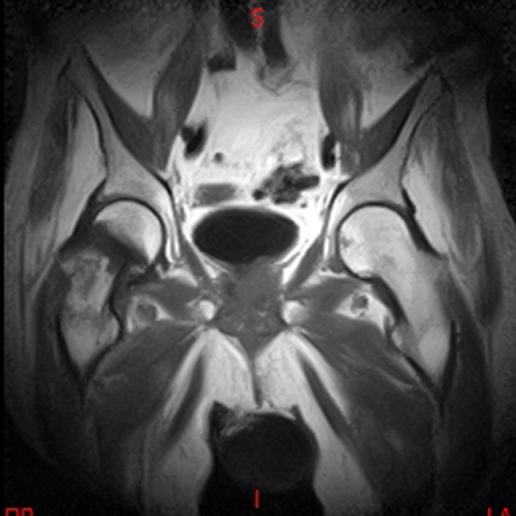

• Resonancia NORMAL SACROILIACAS COR T2

• Resonancia NORMAL SACROILIACAS  AXIAL T1